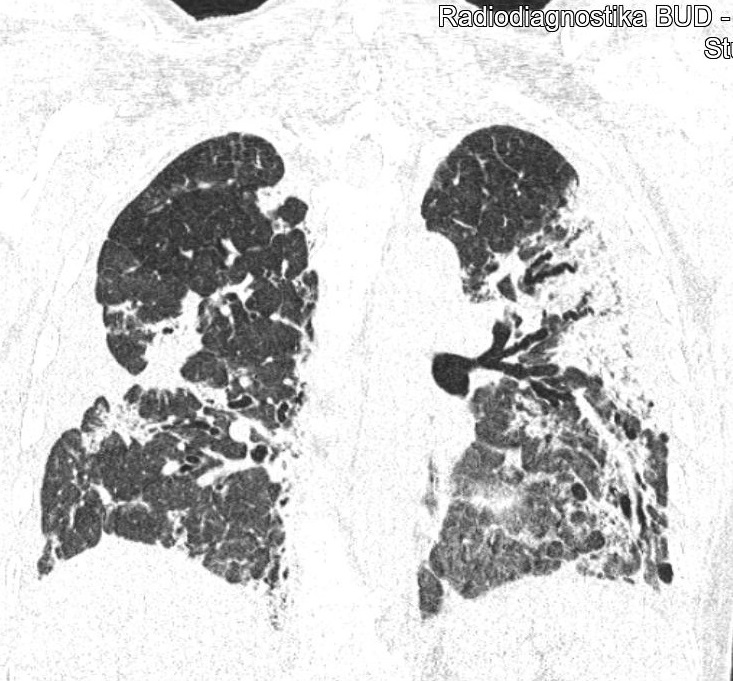

CT snímky vývoje patologických změn na plicích po prodělané nemoci covid-19 u třiapadesátileté doposud zcela zdravé pacientky (fotografie CT nálezu publikovány se svolením Dr. Evy Kočové, Ph.D. – RDG klinika):

Obr. 2: Většina tkáně obou plic je po více jak měsíci od začátku onemocnění stále zánětlivě postižená.